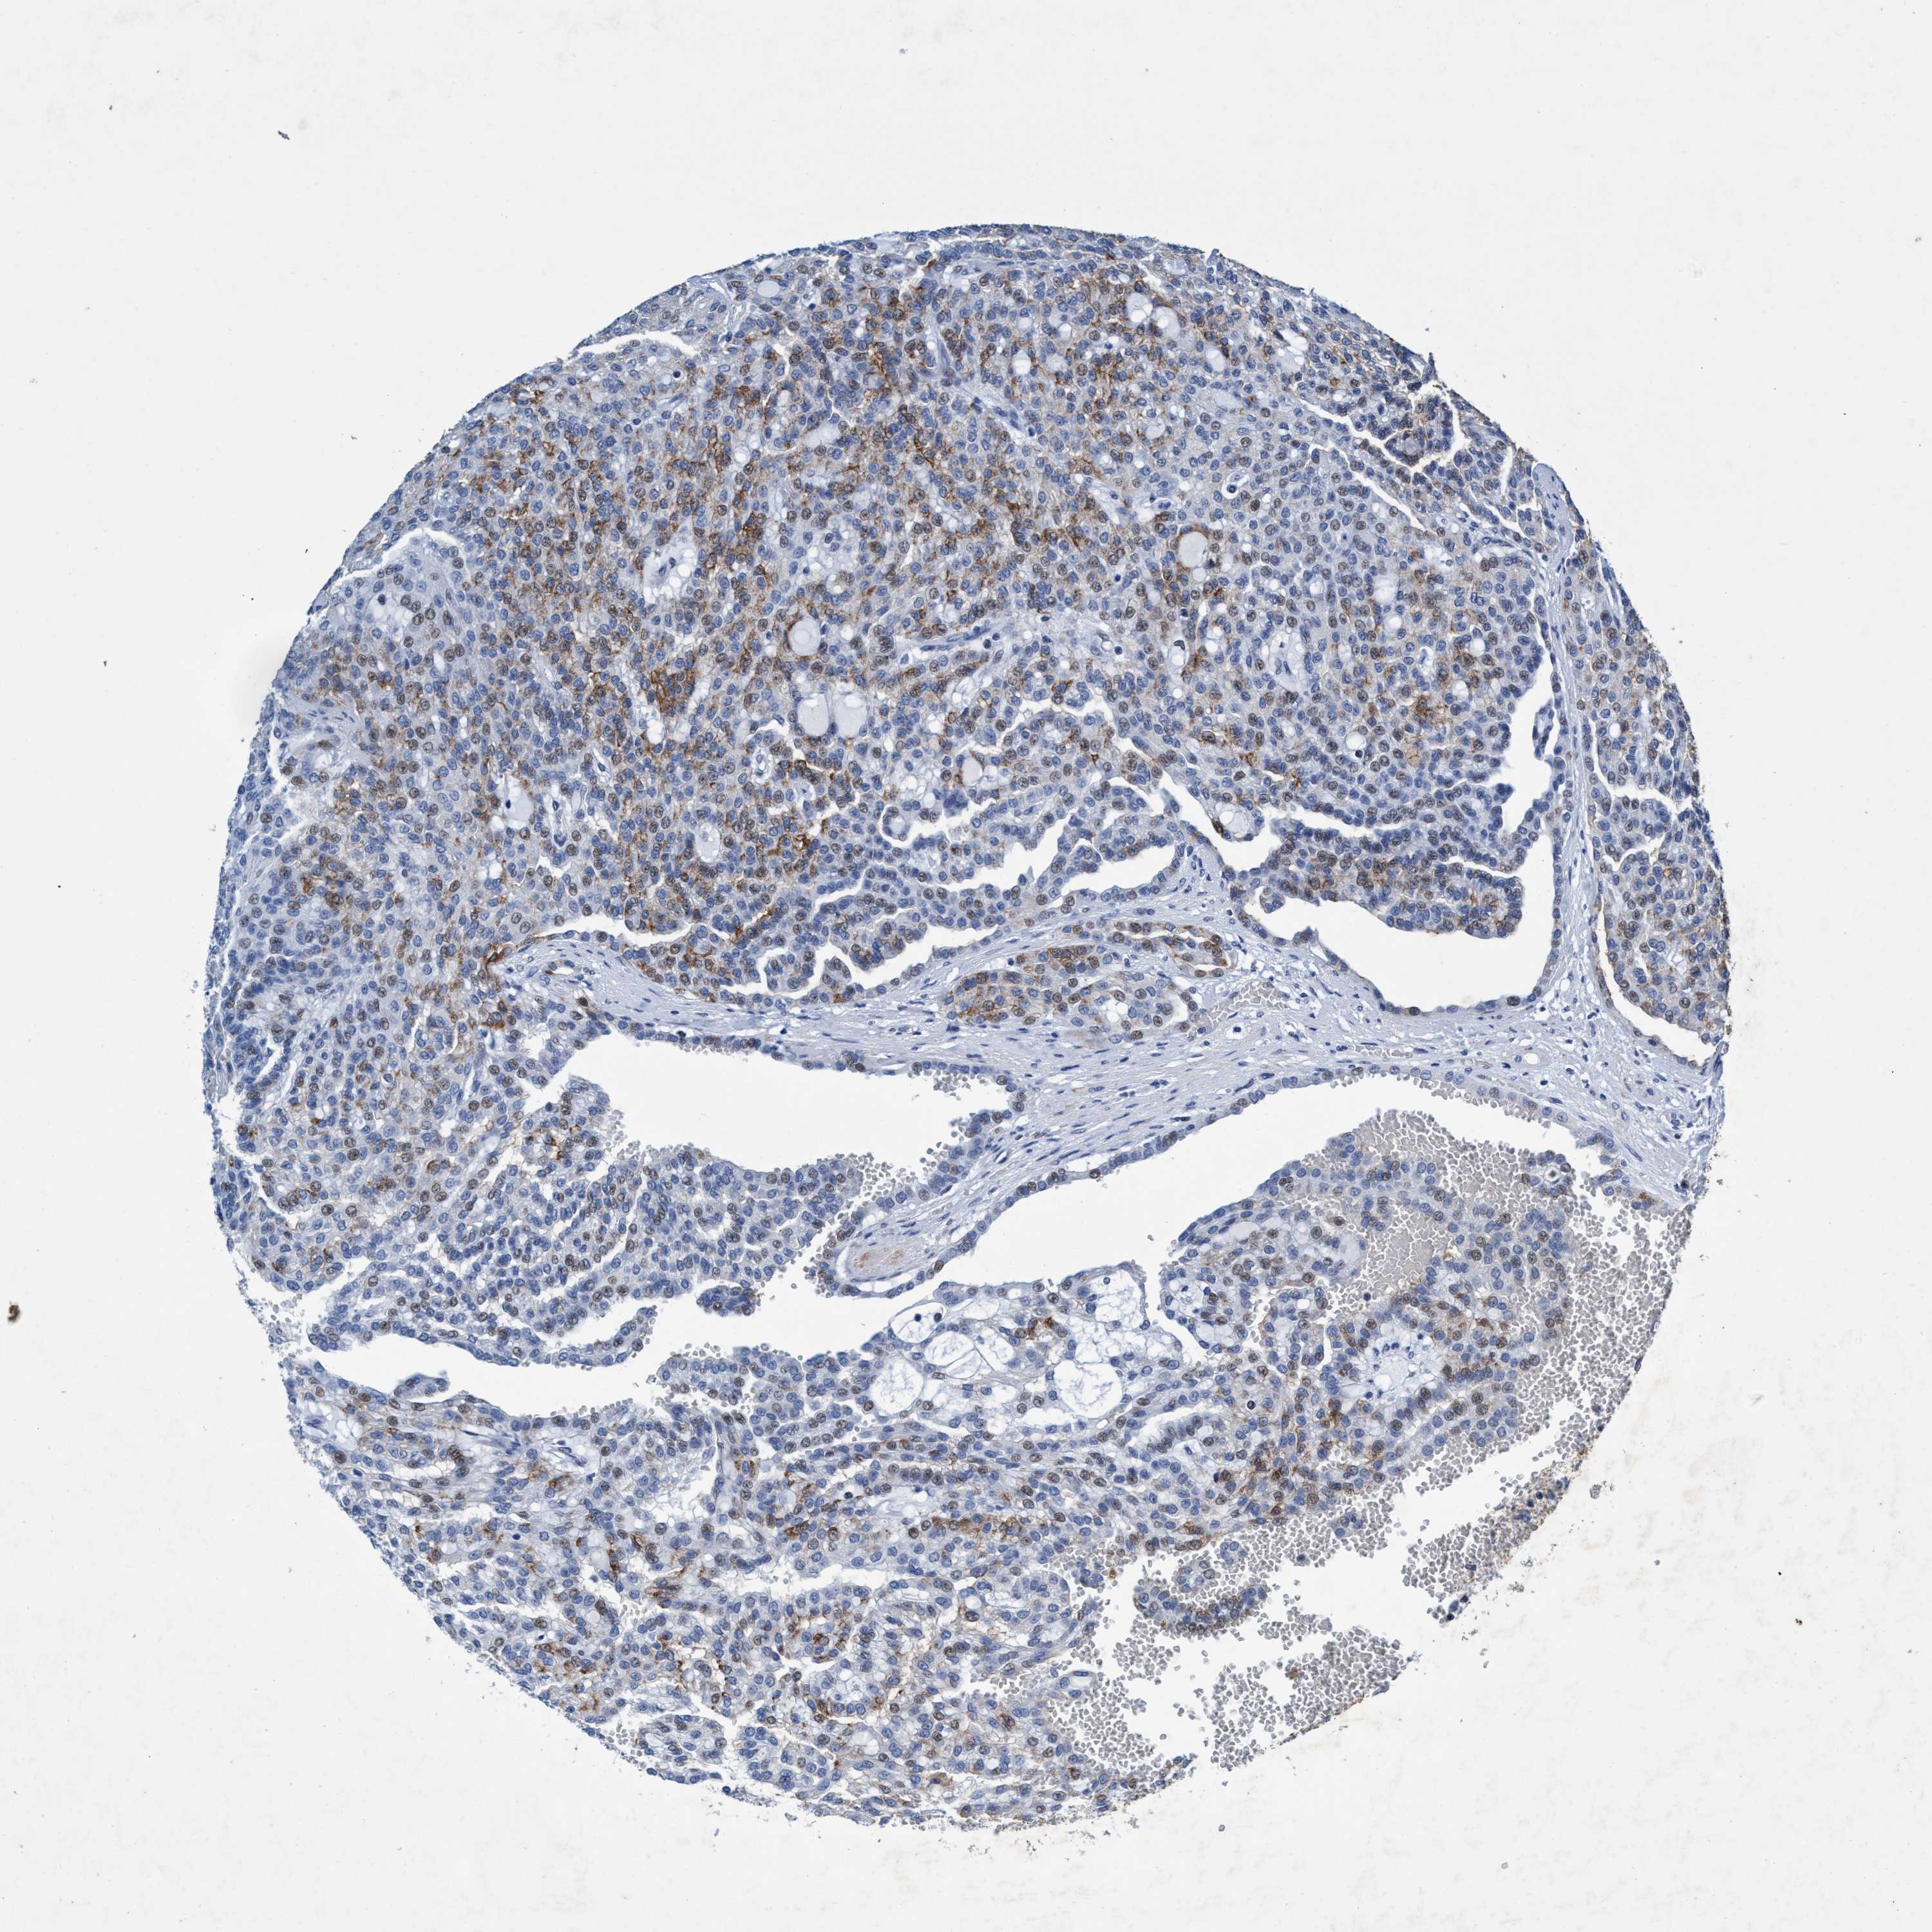

GRB14

CANCER RENAL CANCER Show tissue menu

KICH TCGA KIRC TCGA KIRC VALIDATION KIRP TCGA PROTEIN RCC CPTAC PROTEIN EXPRESSION

ANTIBODIES

AND

VALIDATION